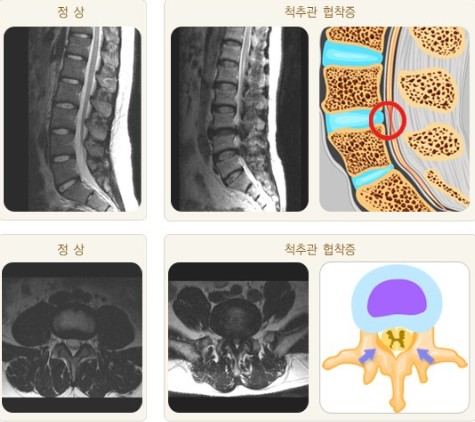

협착증 환자는 척추관을 둘러싼 그 부근 전체, 뼈, 인대, 후관절, 디스크 등이 깡그리 으로 퇴보되어 두꺼워지므로 다리로 가는 신경이 눌려서 근력이 약화되고 근육이 위축됩니다.

퇴행으로 기인해서 뼈도 골극이 자라 두꺼워지고, 후관절도 두꺼워지고, 척추관 안에 있는 인대도 두꺼워지고, 앞에 있는 디스크도 수분이 빠져 납작해지면서 척추관 공간 안을 좁게 만들고요. 이렇듯 척추관을 둘러싼 근처 전체가 다 두꺼워지고 해서 척추관이 좁아질 수밖에 없는데요.

그리고 척추관이 좁아지니까 그 가운데의 신경이 압박되어 신경성 파행, 즉 걸음을 걸으면 다리가 아픈 증상이 나타나게 됩니다.